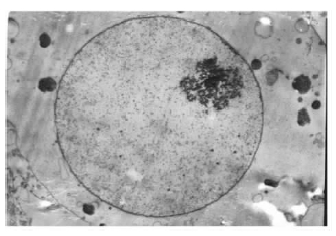

2.3 海马神经元超微结构变化(图 2~4)![]() | 图 2 空白组海马神经元超微结构( 2 800 × ) |

透射电镜下观察可见,空白组神经元核膜完整,核形正常,染色质均匀分布,以常染色质为主,胞浆内各种细胞器均匀分布于核周;牛磺酸组神经元形态学表现与空白组相近;锰组神经元胞体浓缩、胞浆有大量空泡形成,胞核变形、皱缩,核内染色质浓缩、边集,部分神经元胞膜破裂,胞浆内容物释放;牛磺酸+锰组多数胞核形态正常,染色质浓集、核固缩等现象减少,胞浆空泡化程度也比锰组有所降低。

3 讨 论凋亡是由遗传控制、受基因调控的程序性细胞死亡过程〔6〕。本研究通过电镜观察证实了染锰海马神经元凋亡的发生。FCM定量结果表明,神经元凋亡率随染锰剂量的增加呈上升趋势,呈剂量-反应关系,而低剂量锰组与空白组比较差异无统计学意义,推测是染锰剂量较低,尚未达到诱导细胞凋亡的水平。

坏死是非遗传控制的意外细胞死亡。当强烈刺激因素作用于细胞并超过其承受能力时,坏死发生,此时胞膜破裂,胞浆内容物释放,LDH外溢,通过测定LDH活力可反映细胞坏死情况〔6〕。本研究中锰组LDH活力比空白组均明显增高,提示锰可直接引起培养的海马神经元发生坏死,且染锰剂量越高,对神经元的促坏死作用越大。本研究中牛磺酸对锰神经毒性的干预作用主要体现在拮抗凋亡和减轻坏死二个方面: FCM结果表明,牛磺酸+锰组的凋亡率均比同剂量锰组有所下降。电镜观察结果也证实牛磺酸+锰组神经元超微结构有所改善,表明牛磺酸对锰致海马神经元凋亡有一定拮抗作用,在体外实验中也得到证实〔7〕。牛磺酸对神经元坏死的拮抗作用随着染锰剂量增加而减弱:牛磺酸+低剂量锰组LDH活力比低剂量锰组明显降低,而牛磺酸+中、高剂量锰组与中、 高剂量锰组比较,差异均无统计学意义,表明随着染锰剂量增加,神经元受损程度加重,破裂坏死的细胞增多,牛磺酸无法进入神经元胞体而失去干预作用。牛磺酸对神经元的产生保护作用的机制并不十分清楚,且对不同的神经元作用机制似乎也不同〔8〕。